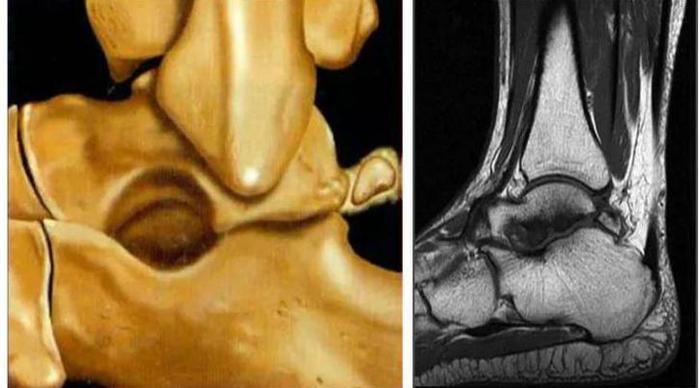

踝关节后方骨性撞击在X线侧位片和CT上均能显示,可发现距骨后方三角形或椭圆形的三角籽骨的病理改变,以及距骨后突是否过长等,MRI时,距骨后突过长伴骨髓水肿在T1WI上呈稍低信号。